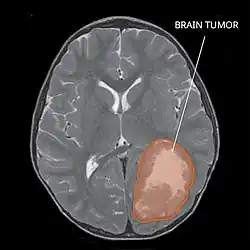

| Primitive neuroectodermal tumor of the central nervous system in a 5-year-old |

The rate of PNETs in not correlated with sex, but it shows a correlation with age.[1] Most cases occur in children around 5 years of age, having a very low frequency in adults.[1] Regarding genetic mutations, a specific type of gene alteration that directly leads to this tumor hasn't been defined yet.[1] However, a positive correlation between individuals with Li-Fraumeni syndrome with a mutation in the gene p53 and PNET has been reported.[2] A significant number of individuals with mutations on the rb tumor suppressor gene have also developed the tumor.[2] Such gene encodes for the protein Rb responsible for stopping the cell cycle at the G1 phase.[6] Another possible contributing factor are mutations in the CREB-binding protein, whose function includes activating transcription,[6] but this interaction still need to be studied further.[2] It has also been presumed that the tumor can arise from cranial irradiation.[2]

Several analysis can be used to determine the presence of the disease. Physical examinations showing papilledema, visual field defects, cranial nerves palsy, dysphasia, and focal neurological deficits are evidences for possible tumor.[2] PNETs can also be spotted through computed tomography (CT) and magnetic resonance imaging (MRI).[2] In images produced by MRIs, an irregular augmentation among a solid mass will indicated the presence of tumor.[3] However, the results of MRIs are usually ambiguous in defining the presence for this specific tumor.[2] In CT scans, the presence of PNETs will be indicated by an elevated density and an increase in volume of the brain.[2] The CT scan can also show calcification,[3] which is present in 41-44% of PNET cases.[2] Since the tumor can be replicated in other parts of the nervous system through the cerebrospinal fluid (CSF), a CSF analysis can also be conducted.[2] A spinal MRI is a fourth type of analysis that is useful in investigating the level of tumor propagation to the spinal cord.[2]